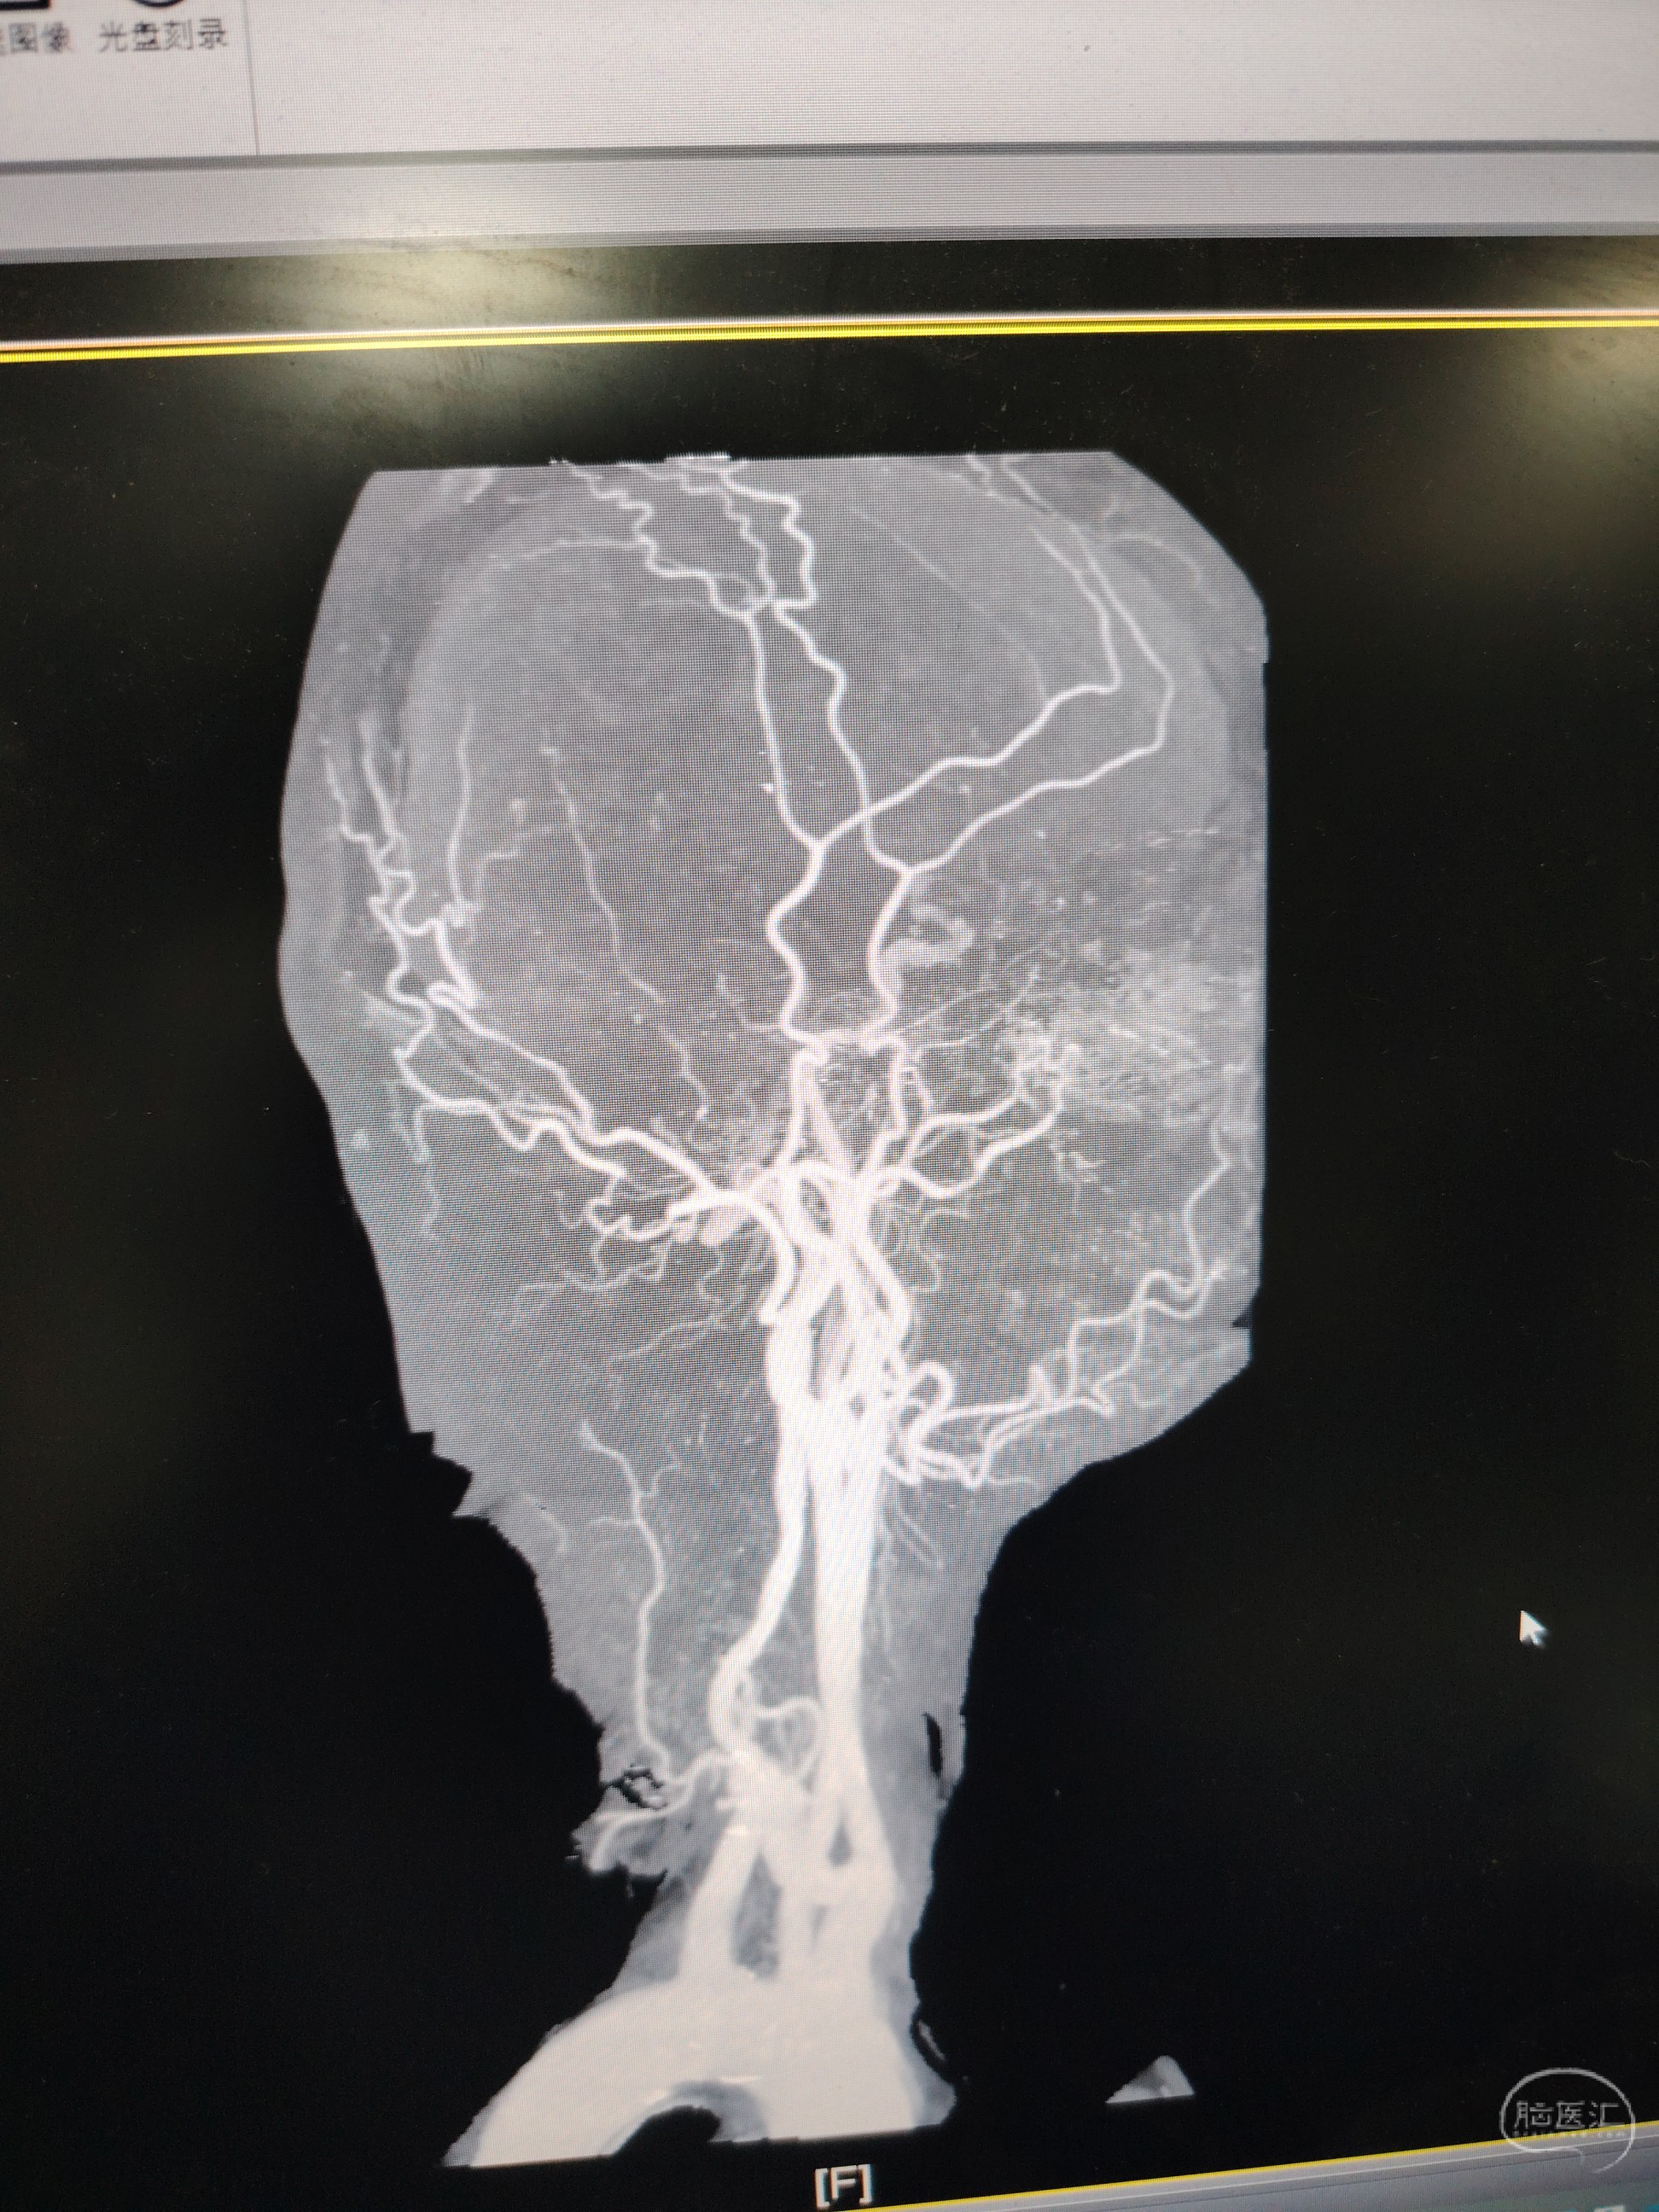

发病前MRA示颅内多发动脉瘤。

急症CTA颅内血管不显影。